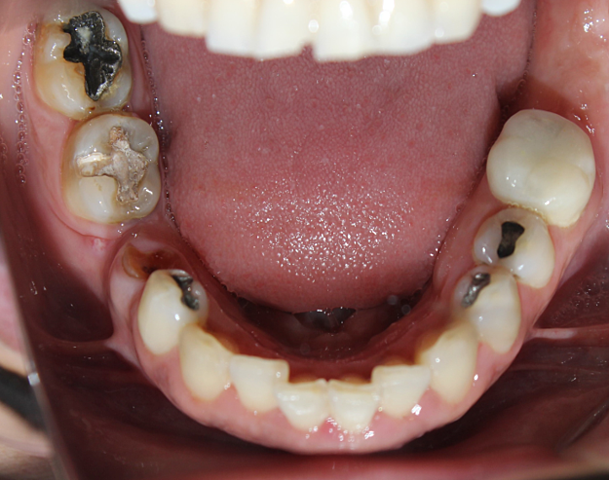

• FOTOS INTRAORALES

FOTOS INTRAORALES

Se realiza toma fotografica intraoral, donde se registra que el paciente se encuentra parcialmente edentulo tanto en carcada superior como inferior.

• DIAGNOSTICO

DIAGNOSTICO

El paciente ´resenta edentulismo parcial en ambas arcadas poe ausencia de OD. 1.1, 1.2, 1.4., 1.7, 1.8, 2.4, 2.5, 2.6, 3.7, 3.8, y 4.6.

amalgamas filtradas en OD.1.6,2.6,3.4,3.5,4.8.

Endodoncias previamente en OD. 2.1 y 2.2, lesiones apicales en OD. 1.3, 1.6, 2.3, 3.5, 3.6 y 4.1

curacion provisional de HC: filtrada en OD. 3.7. remanente radicular 4.5